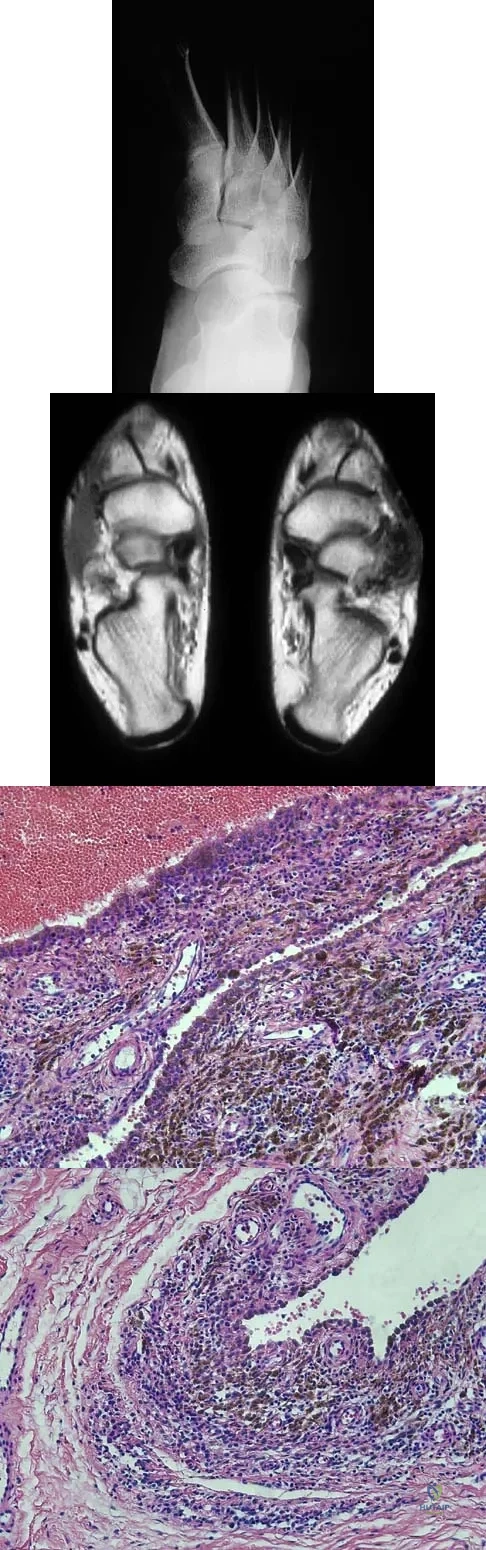

Question 69High Yield

A 16-year-old girl has a painful foot mass. A radiograph, MRI scan, and biopsy specimens are shown in Figures 35a through 35d. What is the most likely diagnosis?

Explanation